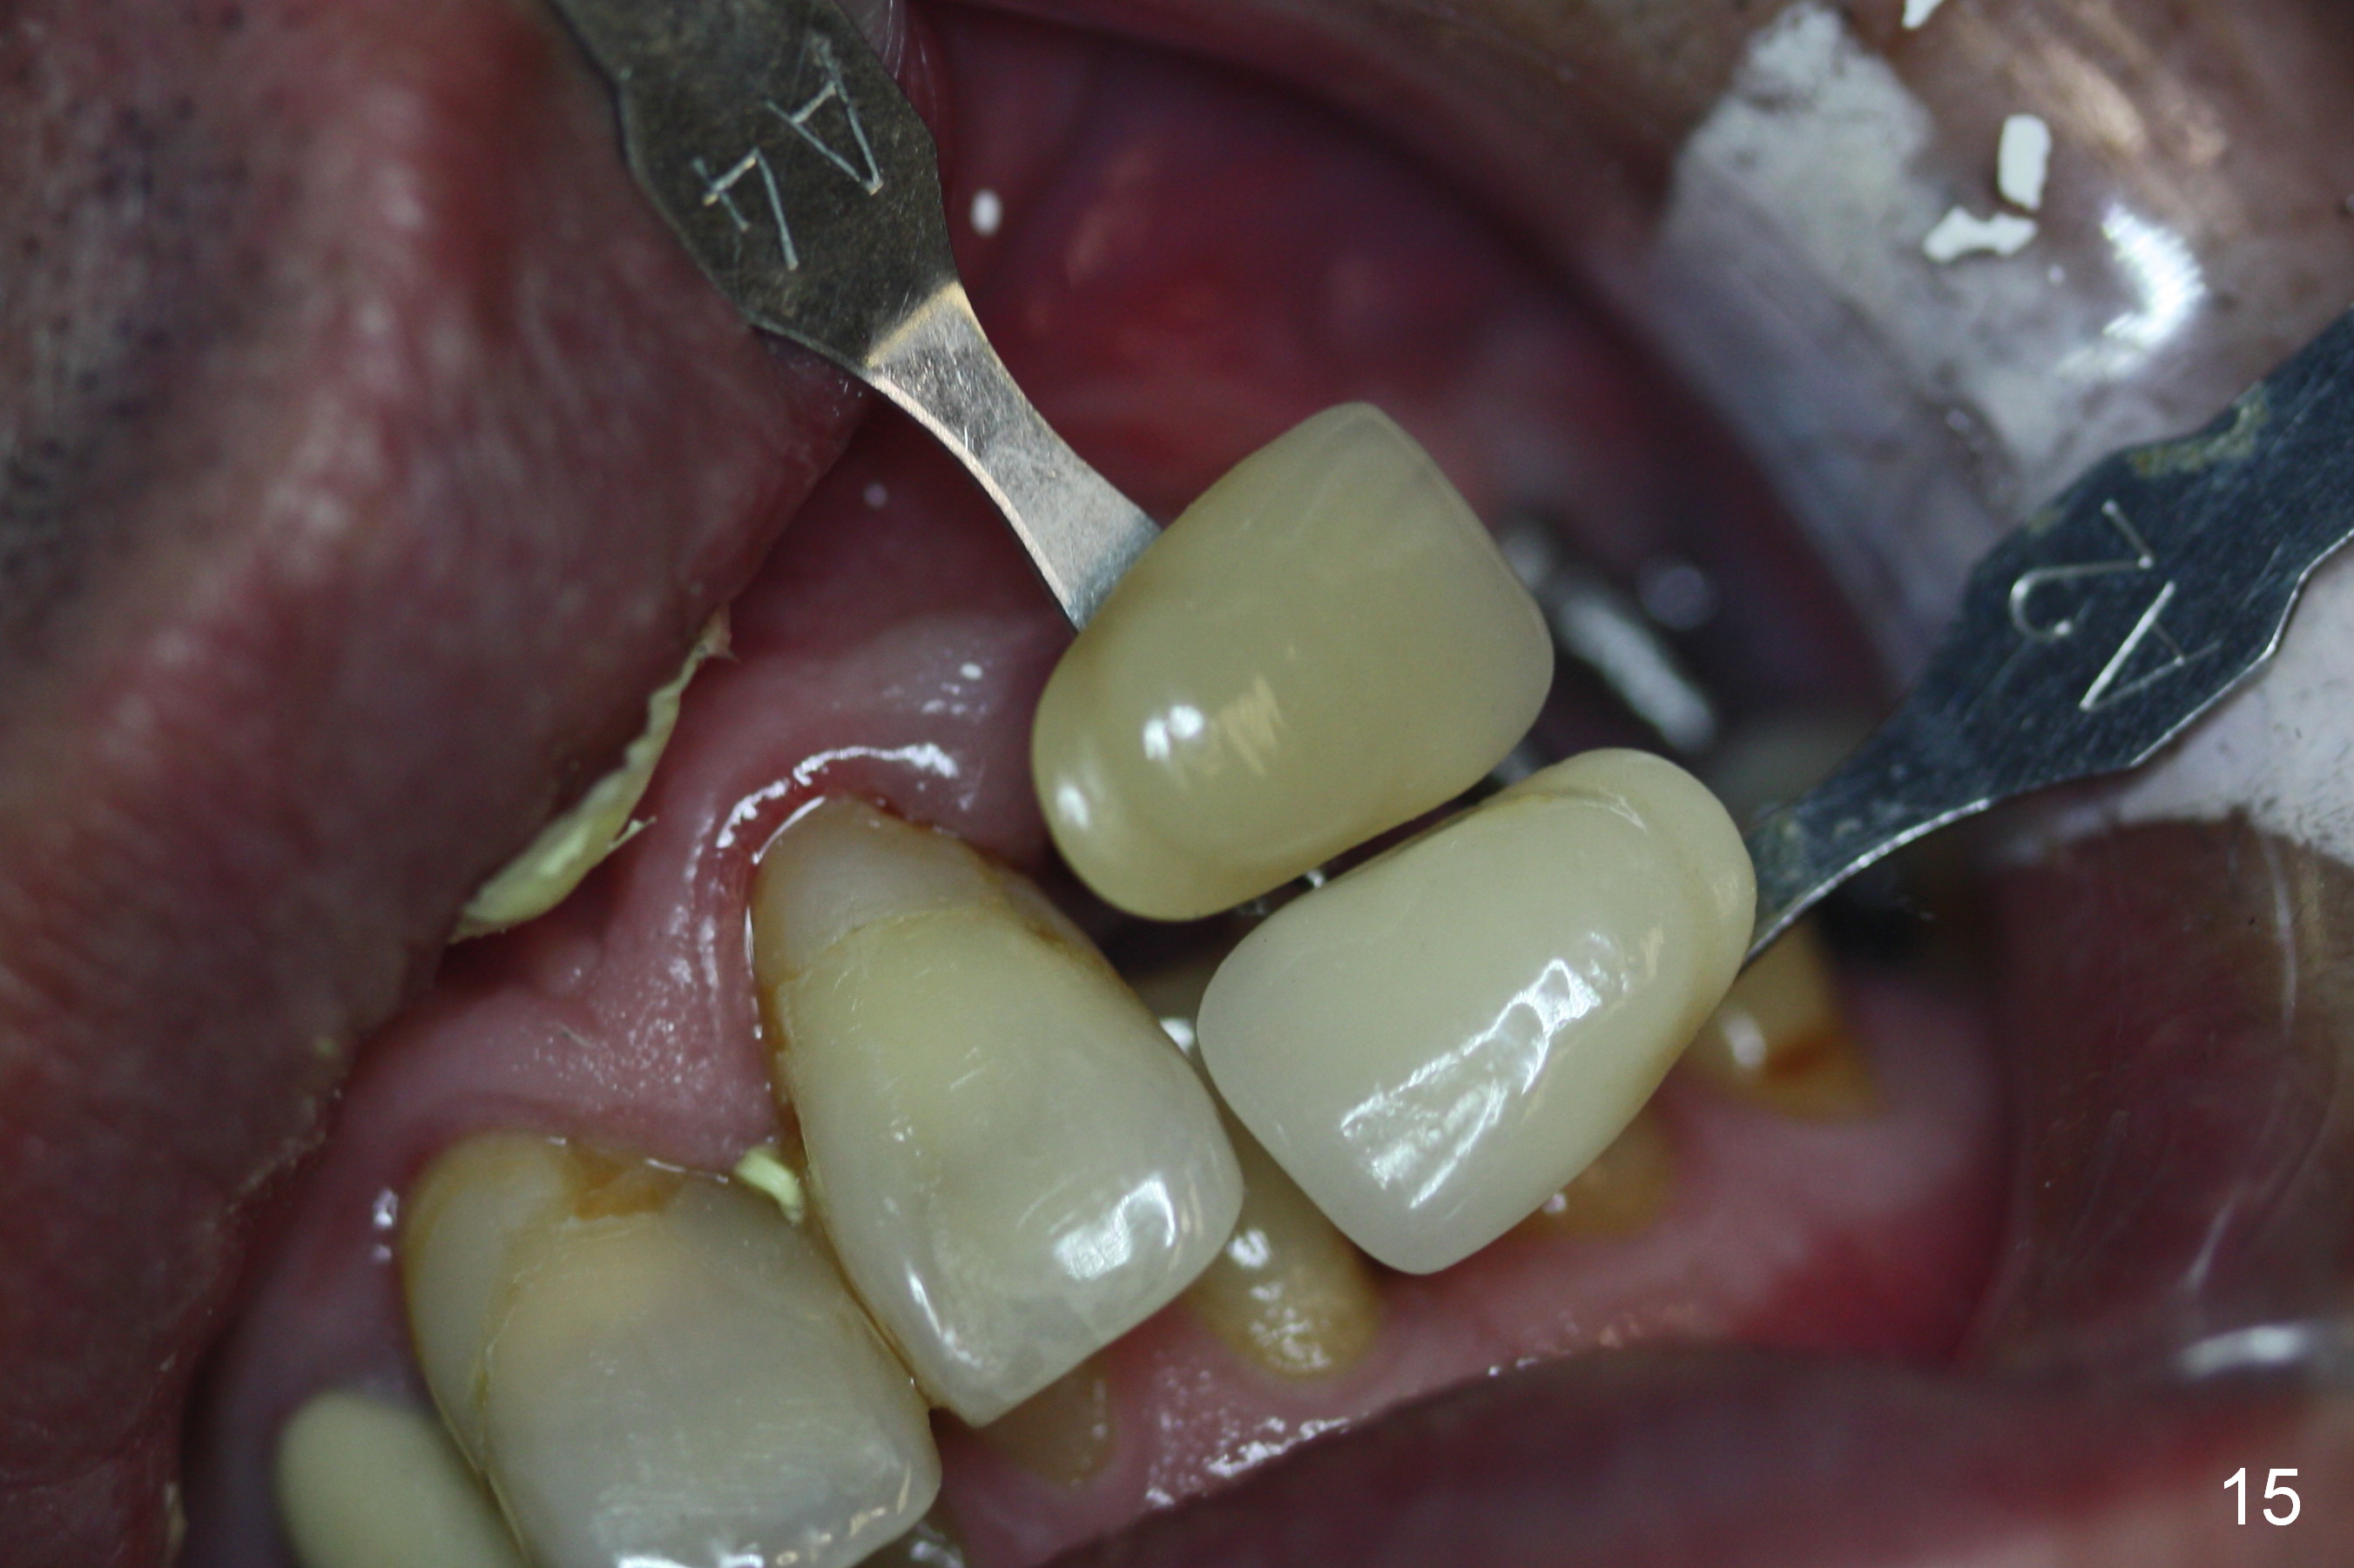

When the patient returns for implant placement (2nd visit after initial exam), he reveals that he is a dental phobic. He requests placement of 4 implants in the upper left quadrant, instead of 2. Narrow ridge is unexpected in the canine and premolar area (Fig.1). Limited bone height at #13 (Fig.3 arrowheads: sinus floor) is found when initial drills are in place (Fig.2,3). A 2-piece implant (4.5x17 mm tissue-level) is placed at #10 after extraction, while 1-piece implants are placed at 11 (3x17 mm (tissue-level, 15 °) and 12 and 13 (bone-level, 2.5x14, 12 mm, respectively; Fig.4,5). In fact the 1 piece implant at #13 is not completely placed (Fig.5). It is removed, the apical 3 threads are cut off (Fig.6 <, since a shorter implant was unavailable in the office) and the remaining implant is re-inserted. The insertion torques of the 4 implants are ~ 60, ~ 35, < 35 and 15 Ncm, respectively. After adjustment (Fig.7), immediate provisionals are fabricated at #10 and 11 (Fig.8, later splinted with composite), while perio dressing is applied around the implants at #12 and 13 and the provisionals at #10 and 11. There is no nasal hemorrhage postop. Although the perio dressing is loose 1 week postop (Fig.9), it is not removed. When the upper lip fissure (Fig.9 <) heals, provisionals at #12 and 13 are planned to be splinted to the other two ones. Two weeks postop, the upper lip fissure heals, the perio dressing dislodges and the implants at #12 and 13 are stable (Fig.10). After abutment height adjustment, a splinted provisional is fabricated over these 2.5 mm 1-piece implants (Fig.11).

The patient returns for final restoration 3.5 months postop; it appears that the implants have osteointegrated (Fig.12,13). After reprep, there is no gross buccal plate atrophy at #10 (Fig.14).